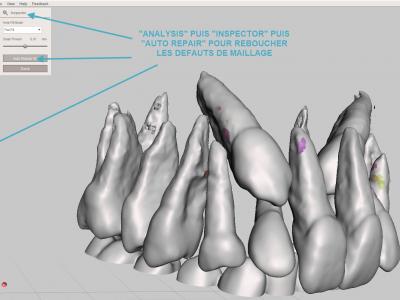

- Etape de réparation : réparer les "trous" du maillage 3D avec l'outil "Inspector" et "Auto repair all" afin de ne pas avoir d'erreurs d'impression